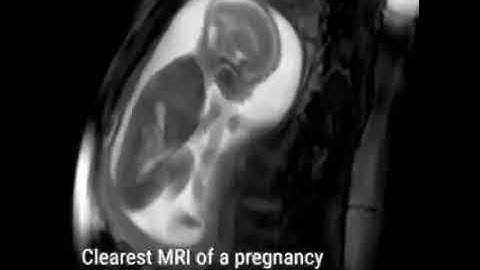

fetal video||MRI scan|| Radiology notes